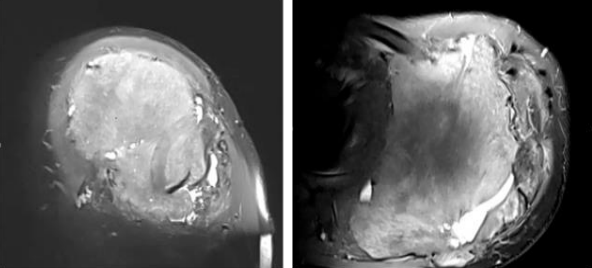

Case 1- 21 year old male who presented with pain and swelling over the left scapular area , was diagnosed with left scapula fibromatosis underwent wide local excision of tumour in 2014 after clinico-radiological evaluation and post-op histopathology confirmed to be Intra-osseous fibromatosis, after 6 years patient presented with pain and local swelling and upon evaluation with X-ray Fig-2  and MRI which showed Hyper-intense lesion on T2 sequence measuring 11.2x14.5x11.3cm with destruction of scapula body and spine with soft tissue deep to the deltoid - coronal and axial images Fig-3 and Biopsy confirmed to have local recurrence and considering chance of recurrence again patient underwent Type 3 intra-articular scapulectomy with gross histopathology image and microscopic image Fig-4. And currently on 3 year follow up and no local recurrence.